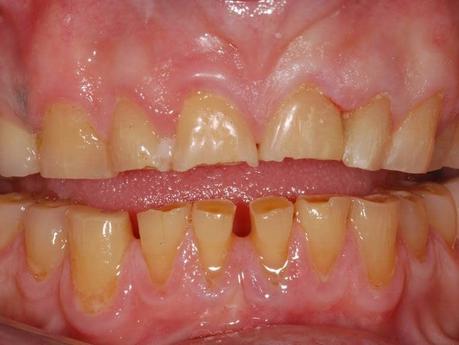

- Incluso antes del año la persona ya ha sufrido de gingivitis, lo cual con el pasar del tiempo puede provocar daños severos en las encías.

- En un año los dientes ya tienen agujeros, grietas, la placa no es el principal problema sino la inflamación de las encías que a su vez adoptan un color rojo muy oscuro.

Es la inflamación de las encías y a simple vista se puede notar debido a la inflamación y enrojecimiento de dicha parte de la dentadura.

Es básicamente la infección de las encías, pero es un cuadro grave.

En esta enfermedad la infección ya ha alcanzando tejidos y hueso, lo peor que puede pasar es que se desprendan los dientes..